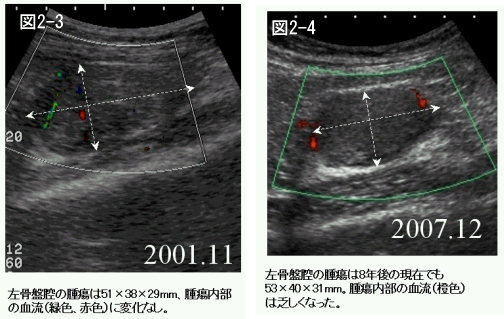

平成13年(2001年)11月では、5.1×3.8×2.9cmで腫瘍の大きさに変化は無く、腫瘍内の血流に変化は認められませんでした。(図2-3)

腫瘍マーカーのSTNは87U/mlでした。

平成19年12月(2007年)ではSTNが100U/mlと上昇気味ですが、超音波検査では同位部に5.3×4.0×3.1cm大のほぼ同様の充実性腫瘤が認められ、拍動流はまばらで遅い状態でした。(図2-4)